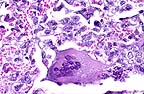

Multinucleate giant cell characterstic of morbillivirus infection. Several nuclei contain eosinophilic intranuclear inclusions. (HE, 400X, 52K)

Histologically, PPR is characterized by necrosis of oral and intestinal epithelium and a generalized lympholysis. The pneumonia which occurs with PPR, like that associated with canine distemper or measles, is "bronchointerstitial", with disorganization of bronchiolar epithelium, and hyperplasia of type II alveolar cells. Although multinucleate syncytial cells may be see in many organs, they are most numerous in lung. Eosinophilic viral inclusion bodies may be either nuclear or cytoplasmic and are present in a variety of cell types.

Moribilliviruses possess two proteins which facilitate binding to host membranes, hemagglutinin and F protein. The F protein mediates fusion of the viral envelope with the cellular membrane and assists in viral attachment. It also causes host cell fusion and is responsible for the formation of syncytial cells. The ability to fuse host cells allows the virus to spread without being exposed to antibody. To be biologically active the F protein must be cleaved by a host protease into two disulfide-linked polypeptides, F1 and F2. If a host cell lacks the necessary proteases, the virus formed is not infectious, since the F protein is required for viral attachment.